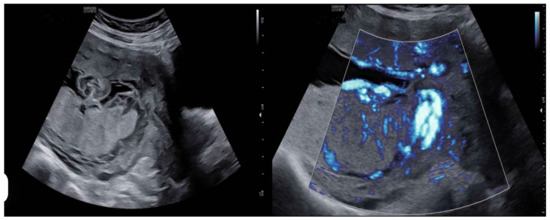

- Prenatal ultrasound evaluation: morphological description of the main placenta and accessory lobe, precise determination of umbilical cord insertion site, color Doppler assessment of vascular connections between lobes, and transvaginal ultrasound to rule out vasa previa.

- Color Doppler assessment to identify vascular connections between lobes.

- Identify vessels traversing fetal membranes between lobes.

- Evaluate the umbilical cord insertion site (central, marginal, velamentous).